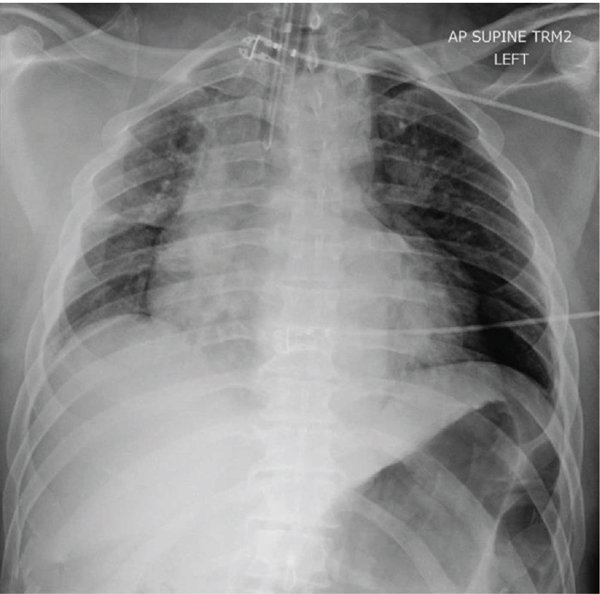

This patient is a 54-year-old homeless man with a history of schizophrenia who presented to the emergency department in November 2020 after being found down with a penetrating injury to the left anterior chest. On arrival, his GCS was 3, and he was being ventilated via bag valve mask by EMS. He was promptly intubated for airway protection. His vital signs were stable. On further exposure, he had an approximately 3 cm stab wound to his left anterior chest, medial to the nipple line, at approximately the level of the 7th rib. Otherwise, he was noted to have ecchymosis of the occiput and superficial lacerations to his right flank. Also concerning was a fixed and dilated left pupil. A pan CT scan revealed a left subdural hematoma with bilateral frontal hemorrhagic contusions and 5 mm of midline shift. Additionally, he was found to have a moderate left-sided pneumothorax and associated left anterior 7th rib fracture for which he underwent chest tube placement with resolution of his pneumothorax (Figure 2). A cerebral oxygenation monitor and drainage device was placed by neurosurgery revealing an elevated opening pressure of 31 mmHg. At this time, there was also concern for possible diaphragmatic injury given the location of his stab wound and imaging findings; however, in the setting of his elevated intracranial pressures, he was deemed unsafe for the OR and admitted to the neuro ICU for further monitoring.

On hospital day 0, his routine workup included a negative COVID-19 nucleic amplification assay. His intracranial pressure was controlled using mannitol and hypertonic saline bullets while he was started on levetiracetam for seizure prophylaxis. Repeat CT imaging the following day showed stability in his intracranial bleeds and a decrease in midline shift. His mental status improved, and he self-extubated on hospital day 3. After his intracranial pressures normalized his drains were removed, and on hospital day 6, he underwent diagnostic laparoscopy to rule out diaphragmatic injury given the location of his initial stab wound. Prior to this procedure, he had a repeat COVID nucleic amplification assay as per institutional policy, which again resulted negative.